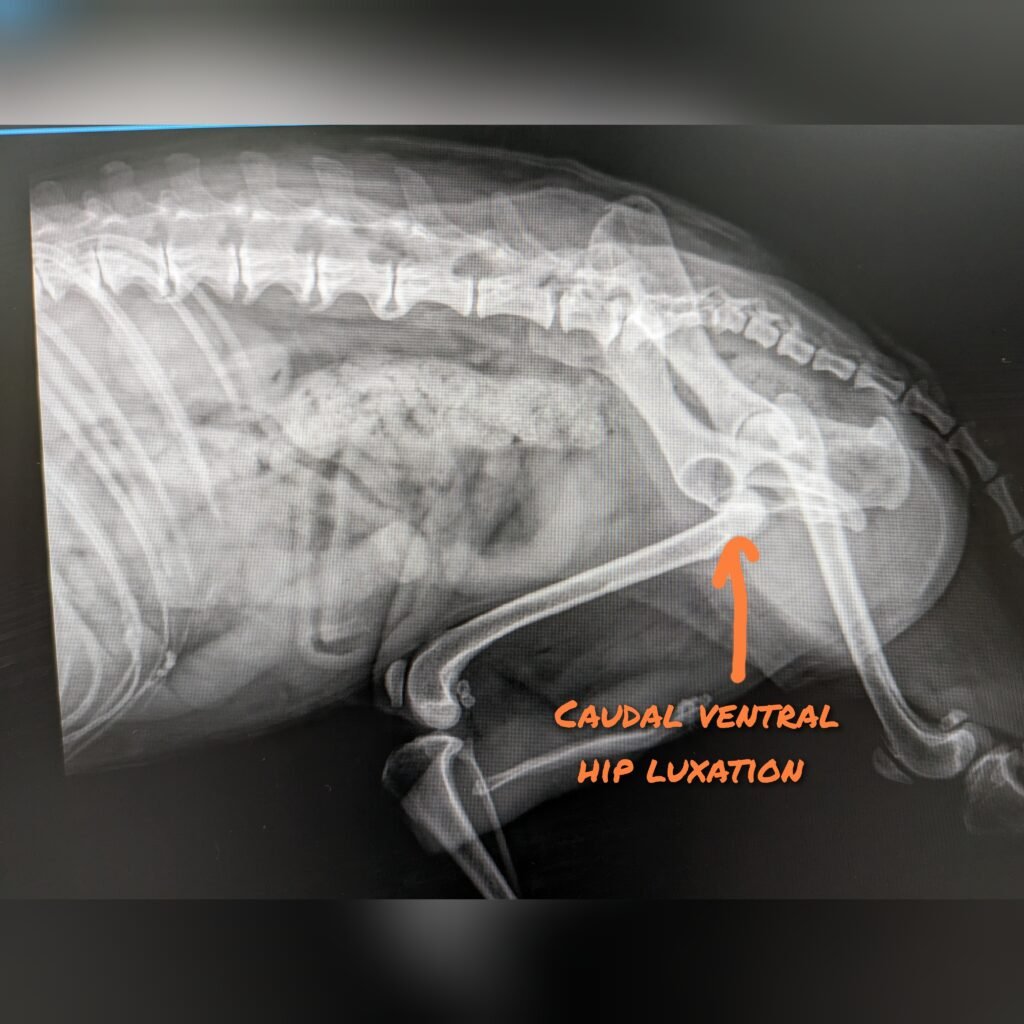

Hip Luxation – caudoventral luxation

Treatment for caudalventral hip luxation is similar to craniodosal luxation. Closed reduction under general anesthesia is recommended for acute, uncomplicated hip luxation. The hind limbs are then placed in hobbles to prevent abduction of the hips for 2 weeks. Cage confinement is also essential for immobilization of the hip. If conservative treatment fails, then surgical options can be considered.

❌Ehmer slings are contraindicated for ventral luxation❌